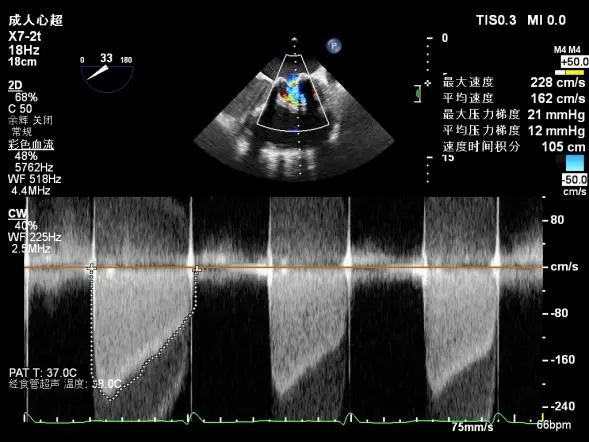

二尖瓣位生物瓣舒张期峰值流速加快,平均跨瓣压差约9-11mmHg,探及瓣周漏(主要源于内侧瓣架)及瓣中反流。三尖瓣位生物瓣舒张期峰值流速大致正常(约1.52m/s),探及瓣周漏(主要源于内侧瓣架)及瓣中反流。探及主动脉瓣及肺动脉瓣反流束。估测PASP约46mmHg(可能低估)。

多普勒检查:二尖瓣位生物瓣舒张期峰值流速加快,平均跨瓣压差9mmHg,峰值跨瓣压差27mmHg,原瓣周漏消失。